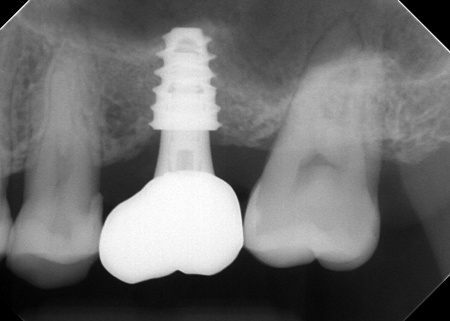

③温存が難しい左上奥歯(第1大臼歯)は抜き、骨を再生させる処置「GBR(骨造成)」を行ったのち、人工歯根を埋め込む「インプラント治療」により噛む機能を回復させます。

左上奥歯1本は抜き、GBRで骨を再生させたのち、インプラントを埋入します。

インプラントに装着する人工歯の素材には、自費診療の白いセラミックを選択しました。